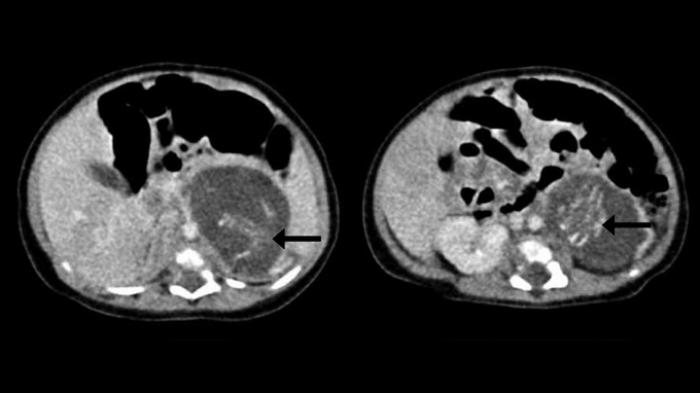

Caz incredibil în China, unde o fetiţă nou-născută a venit pe lume însărcinată cu gemeni. În spitalul Regina Elsabeta din Hong Kong a fost adusă pe lume o fetiţă care era gravidă cu doi gemeni în opt săptămâni.